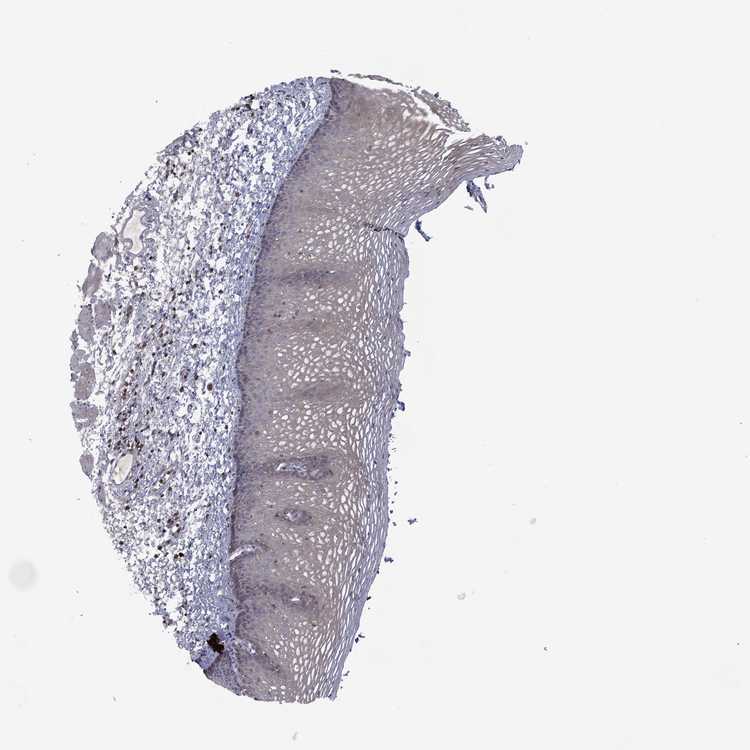

TISSUE PRIMARY DATA ESOPHAGUS Show tissue menu

Esophagus

ESOPHAGUS - Antibody stainingi

Antibody staining in the annotated cell types in the current human tissue is reported as not detected, low, medium, or high, based on conventional immunohistochemistry profiling in selected tissues. This score is based on the combination of the staining intensity and fraction of stained cells.

Each image is clickable and will lead to virtual microscopy that enables deeper exploration of all samples and also displays staining intensity scores, fraction scores and subcellular localization as well as patient and tissue information for each sample.

Antibody HPA003218Antibody HPA073349

Squamous epithelial cells Not detectedNot detected